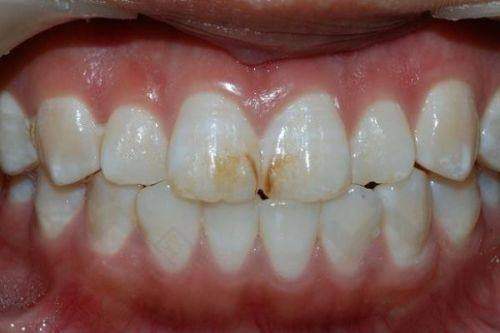

洗牙的学名是口腔牙龈洁治,是治疗牙龈炎和牙周病较基本的方法,可清除牙结石和牙菌斑。重庆理想口腔医院提供多种洗牙方式,不同方式价格有所不同。超声波龈上洁治的价格一般在200 - 400元左右,手动龈下刮治的价格一般在800 - 1000元左右,牙周治疗仪的价格一般在2000元左右。作为口腔专科,一般300元以内可完成基本清洁。

洗牙过程包括洗、刮和根面平整。洁治是用超声波洁治器去除龈上结石,刮治是用刮治装置去除龈下牙垢,去除牙垢后还需进行抛光。这样能让牙齿更加清洁,预防口腔疾病的发生。和长寿区其他牙科相比,重庆理想口腔医院在洗牙价格上有一定的优势。像长寿附大口腔超声波洁牙120元起,虽然价格看似更低,但重庆理想口腔医院在洗牙的项目和设备上可能更具特色。